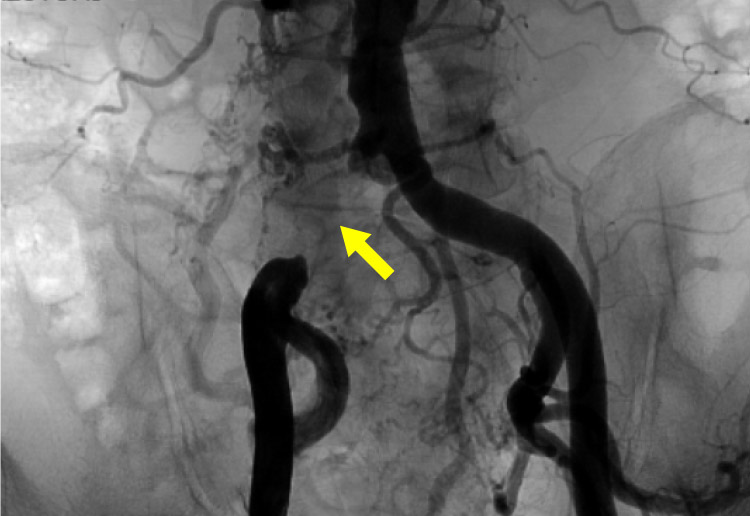

経皮的血管形成術(EVT)

狭くなった血管や詰まった血管に対して、カテーテルを使い、バルーンで拡張したり、ステント(金属の筒)を留置する治療を行います。石灰化が高度な病変には、バルーンだけでは拡張しにくいため、CROSSER(振動で石灰化を軟らかくする器具)を用いて治療することがあります。

閉塞している血管に対してワイヤーを通過させバルーン拡張し最終的にステントを留置し血管を拡げ、血流を改善します。

CROSSER